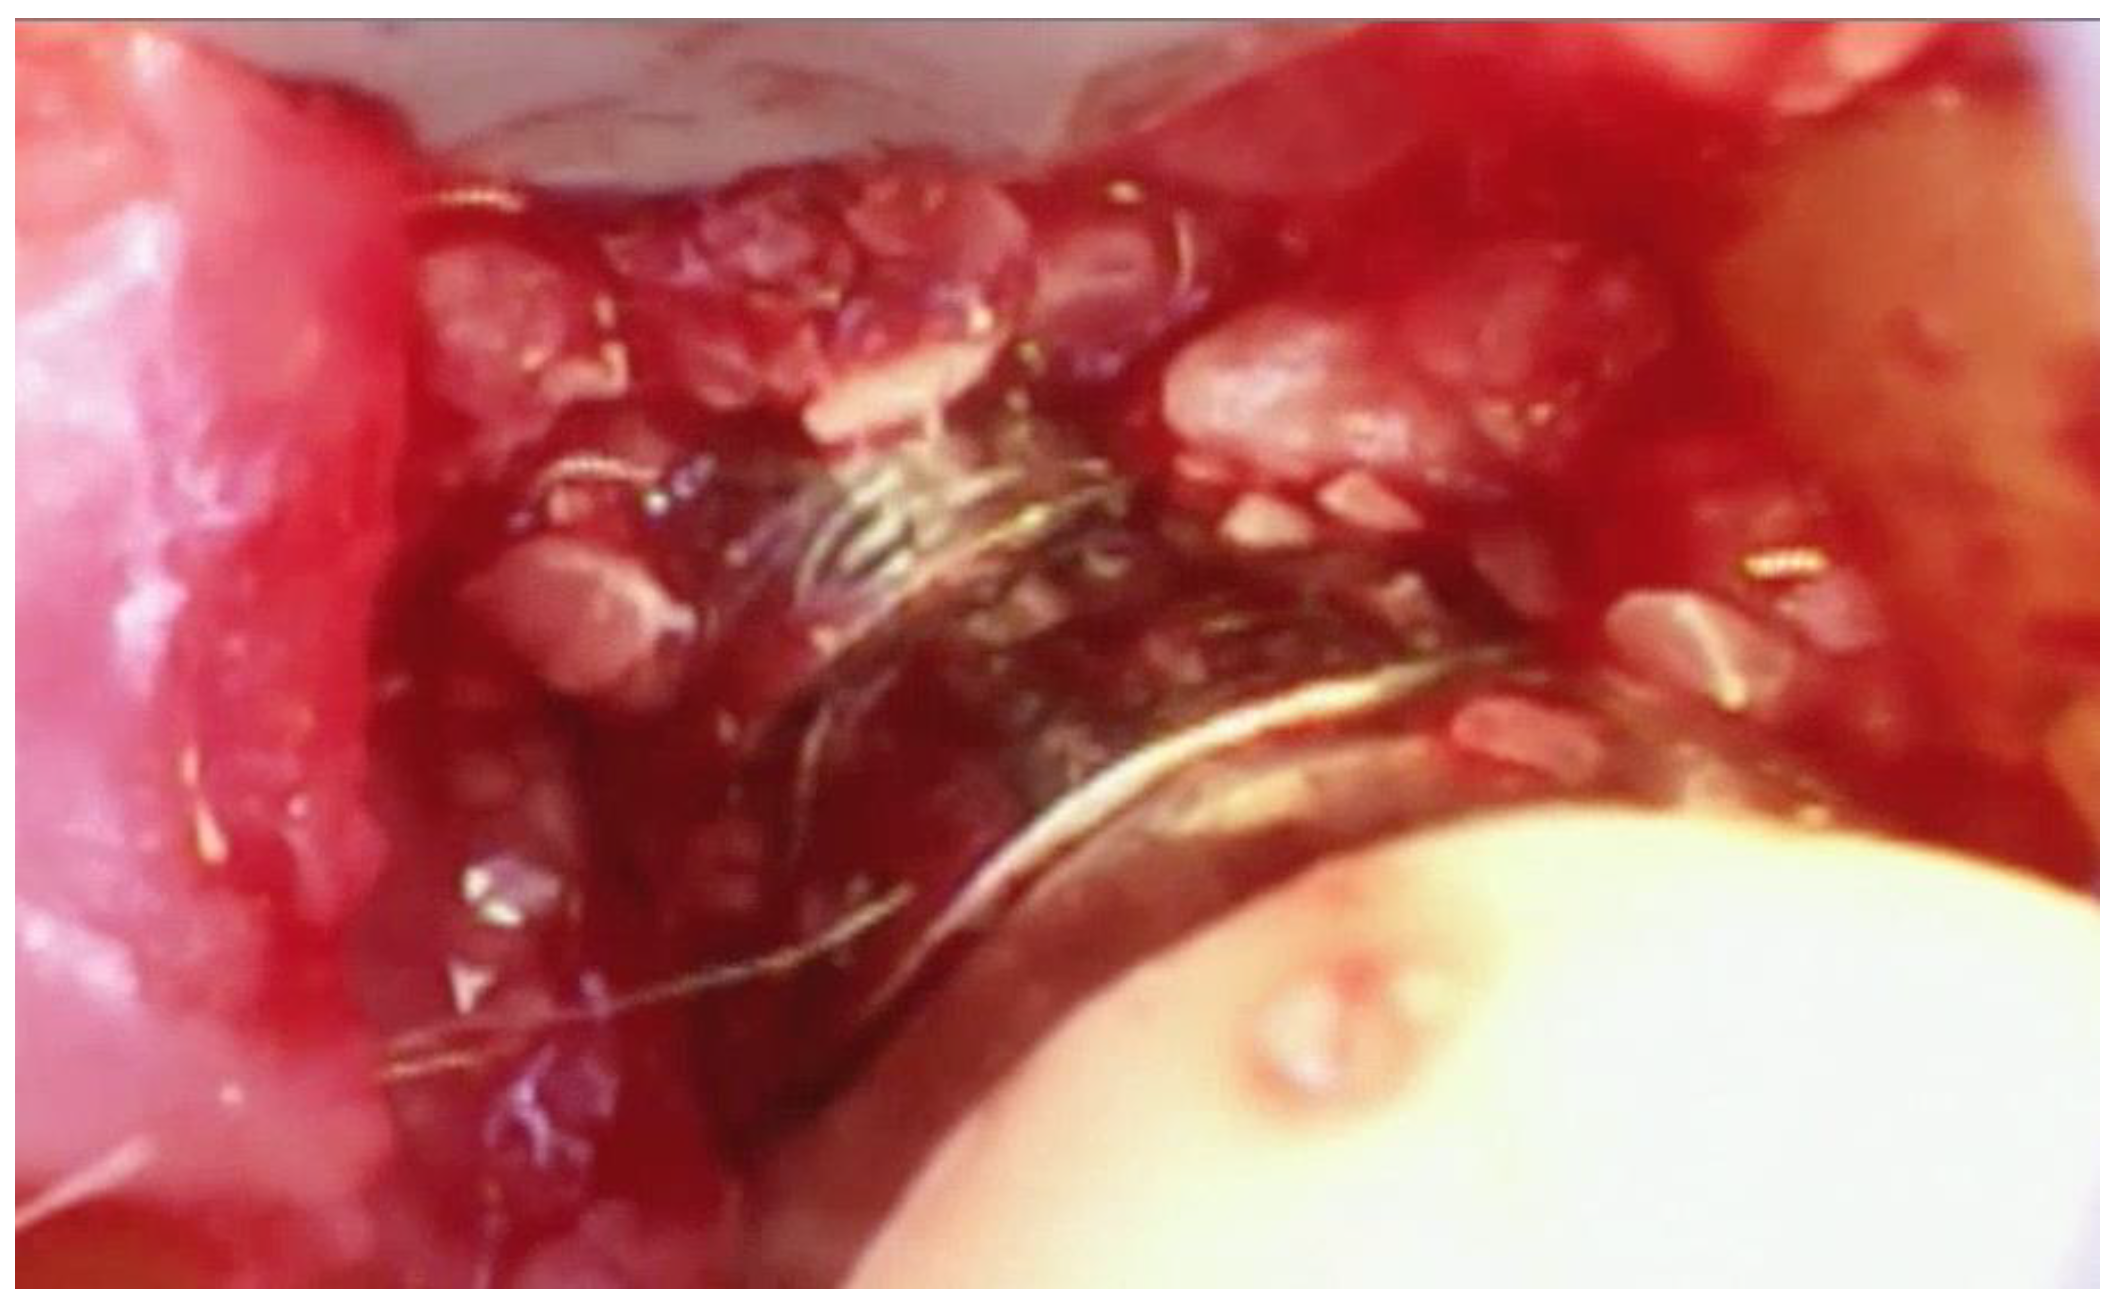

Once the implant has been adequately visualized, under videoscope guidance and using a new small blade, a thin section of tissue approximately 1–2 mm in thickness is removed from the tissue that was in contact with the implant in the area of bone loss. (Figure 7) When this tissue is evaluated histologically, as was done in the study by Wilson et al., multiple areas of cement and/or titanium particles surrounded by inflammatory cells are often noted. The purpose of removing this tissue is to eliminate foreign material that may cause further damage to the implant-supporting bone in the future as well as may interfere with the regeneration of bone around the implant.

Figure 7. A thin (1–2 mm) section of tissue (arrow) containing foreign particles of titanium or cement is removed from the area of bone loss.